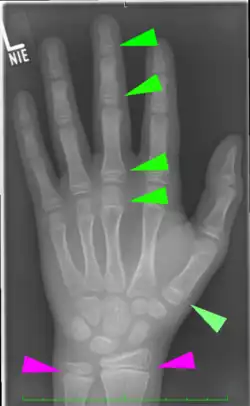

Für die Beurteilung auf Röntgenaufnahmen der am Handskelett des Menschen darstellbaren Epiphysenfugen gibt es spezielle Atlanten, die das chronologische Alter eines Kindes mit dem aktuellen Skelettalter vergleichen lassen (Abb.) Aufgrund der Vielzahl von Wachstumsfugen an den Handknochen, die sich alle zu unterschiedlichen Zeitpunkten knöchern verschließen, ist hier eine Zuordnung in Halbjahresschritten möglich.[4] Damit können, zusammen mit aktuellen Längenmessungen von Körpergröße, Sitzgröße, Beinlänge etc., Aussagen über das noch zu erwartende Gesamtwachstum des Kindes oder des Jugendlichen gemacht werden. Aufgrund der unterschiedlichen Geschlechtsentwicklung bei Mädchen und Jungen ist der Reifungsprozess und damit das Skelettwachstum bei Mädchen früher abgeschlossen. Die ersten Epiphysenfugen schließen sich bei Mädchen um das 14. Lebensjahr, die letzten Fugen beim Jungen nach dem neunzehnten Lebensjahr.